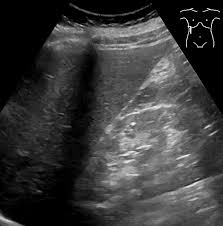

복부 초음파는 비침습적이며 방사선 노출이 없는 안전한 검사 방법으로, 초음파(ultrasound)를 통해 복부 내 장기들의 상태를 실시간으로 확인할 수 있는 진단 도구입니다. 복부 초음파로 알 수 있는 것 중에서는 특히 간, 담낭, 췌장, 비장, 신장, 방광, 대동맥, 소장, 대장 등의 상태를 파악할 수 있으며, 질환의 조기 발견에 탁월한 효과를 보입니다.

간 관련 질환

- 지방간: 간 조직 내 지방 축적 상태 확인 가능

- 간경화: 간 표면의 거칠음, 크기 변화, 비장 비대 여부 등 확인

- 간암, 간종양: 실질 내부에 덩어리 유무 탐색